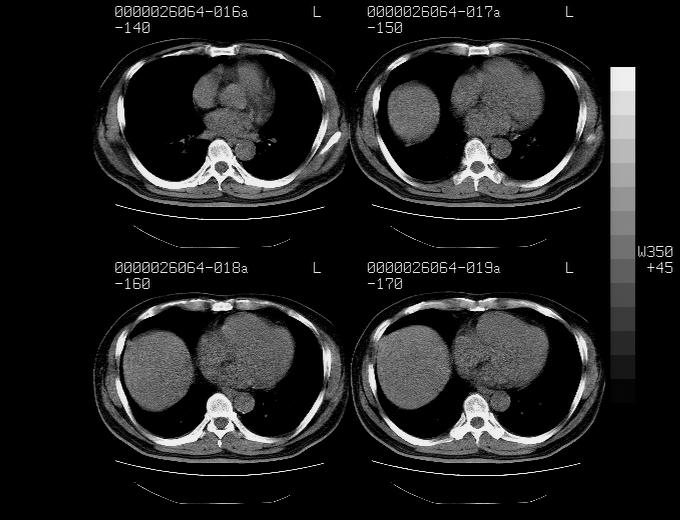

患者,男性,71岁,因咳嗽而就诊,

典型的右肺中心性肺癌并纵隔淋巴结转移

右肺中心性肺癌并纵隔淋巴结转移可能性大!

病灶中等程度强化 还是支持肺癌诊断

考虑右肺中心性肺癌并右肺门及纵隔淋巴结转移。

1,右肺中心型ca,气管隆突旁淋巴结转移。